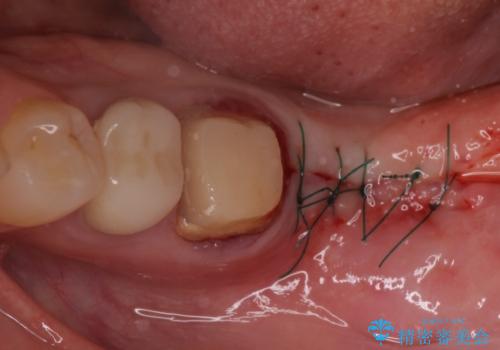

手前は根管治療後に補綴治療を、奥は骨造成後にインプラント埋入し、手前の歯と同時に補綴治療を行うこととしました。

インプラント埋入にあたり、歯槽骨での炎症が広範囲であったことから、事前に骨造成を行いました。

歯槽骨の高さや幅を回復することができ、望ましい位置にインプラントを埋入することができました。